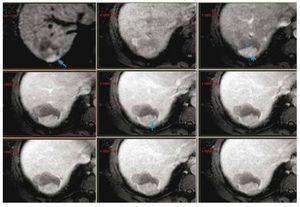

Paciente masculino de 42 años de edad, previamente santo. Debutó en septiembre del 2010 con melena, sin tratamiento. En enero del 2011 presenta un cuadro de hematemesis, se inicia estudio documentando várices esofágicas en endoscopia superior. Se realizó ultrasonido donde se encuentran datos sugerentes de hipertensión portal. El 22 de abril del mismo año, se documenta infección por virus de hepatitis C. Se inicia seguimiento por imagen y en junio del 2011 se documenta lesión en tomografía con comportamiento típico de hepatocarcinoma en el segmento VII, de 6 cm de diámetro (fig. 1). El paciente se encontraba en clasificación B de la Clínica de Barcelona.

Figura 1. Tumor en segmento VII del hígado de 6 cm de diámetro. En TC contrastada presenta comportamiento típico de CHC por criterios de imagen.

En agosto 2011, se realiza quimioembolización presentando respuesta parcial en el estudio de seguimiento a 3 meses. Se realizó QEIA nuevamente en diciembre 2011 (fig. 2). En seguimiento, se observa zona de captación en la periferia del tumor, en territorio subdiafragmático (fig. 3); en marzo del 2012 se decide realizar nueva QEIA. Por la localización de la zona con actividad, se realiza angiografía selectiva de probables ramas accesorias. En angiografía previa a la embolización, se identifica irrigación de la zona de actividad por parte de la arteria frénica derecha (fig. 4). Se realiza embolización blanda y ablación por radiofrecuencia (ARF). Última resonancia magnética dinámica de abril 2013, sin evidencia de activad tumoral (fig. 5).

Figura 3. RM de control. Se observa una zona de actividad periférica en segmento VII, que muestra restricción de la difusión (flecha) y realce arterial y lavado (cabeza de flechas) durante la fase dinámica. La zona hipodensa (*) corresponde a la zona de necrosis posterior a la QEIA.

Figura 5. RM de control, donde se muestra difusión y fase contrastada dinámica. No hay evidencia de realce que sugiera actividad tumoral.